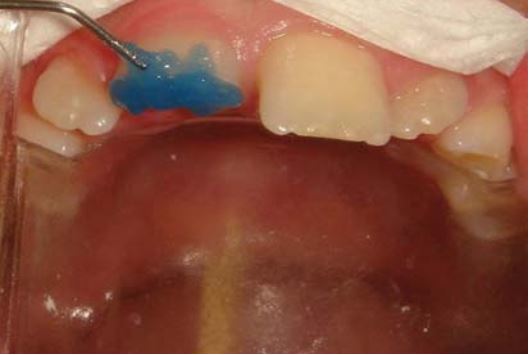

Cả răng cửa và mảnh gãy được khử trùng bằng Chlorhexidine 0.2% trước khi etching và bonding (H18.6 đến 18.11).